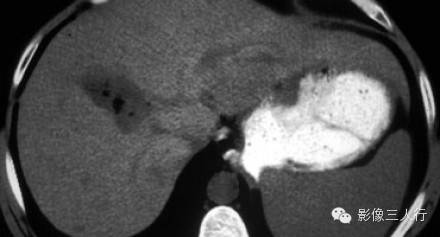

肝脏乏血供比富血管肿瘤常见。大多数乏血供病变是恶性的,转移瘤是目前最常见的。尽管大多数原发性肝肿瘤血供丰富,但也有例外,10%的肝癌是乏血供。胆管癌也是乏血供的,但可在延迟期出现增强(如图)。下图是一个乏血供肿块,在动脉晚期和门静脉晚期表现为不规则强化,这是一个恶性的表现。在延迟期图像肿块中央结构相对致密,说明其强化较正常肝脏慢。这表明肿瘤主要由纤维组织构成。纤维组织使得肝包膜回缩。这些影像表现提示这是一个胆管癌。

下图:平衡期胆管癌相对高密度的瘢痕组织(箭头)。